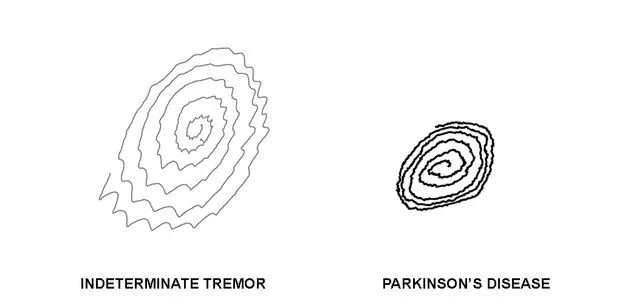

When I went into the examination room, there was an intern on scholarship from Thailand who was moving back to Bangkok in a few weeks and we were chatting about all of the things that he needed to do in New York before going back. I suggested a few Broadway shows, Katz’s Deli, Coney Island. There was an RN in the room too and as we were talking they were having me do all kinds of tests: touching my nose to my face, walking across the room, drawing spirals in a notebook.

“Actually,” said the intern. “You’re showing all of the signs of Parkinson’s.”

When the neurologist came in, she saw the results of the intern’s tests and then repeated many of them herself, confirming his suspicions. “When we think of an essential tremor, we think of someone like Katharine Hepburn… her whole body shakes and even her voice has a warble to it.” I wanted to reply, “The loons, Henry, the loons!”

Instead, I listened as she explained that with Parkinson’s disease (or P.D.) there are two additional components to a tremor: rigidity (or stiffness) and issues with mobility. She pointed out that when she watched me walk down the hallway, my right arm remained completely still while my left arm swung. She’d also lifted both arms and felt that my right arm was heavier. As for mobility, she’d had me rapidly move my thumb up and down on my right hand and then my left hand and I struggled to do it as quickly on my right side. Also my handwriting was getting progressively smaller and smaller the more that I wrote a sentence.